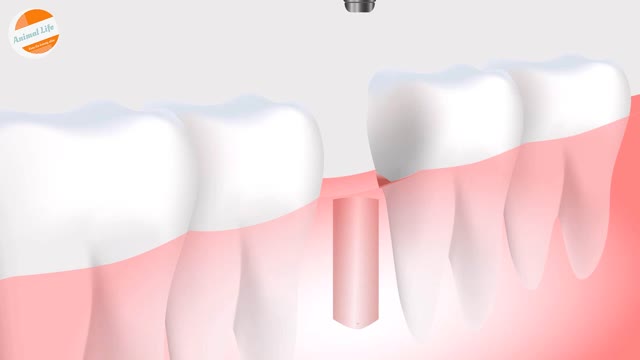

Tooth Insertion